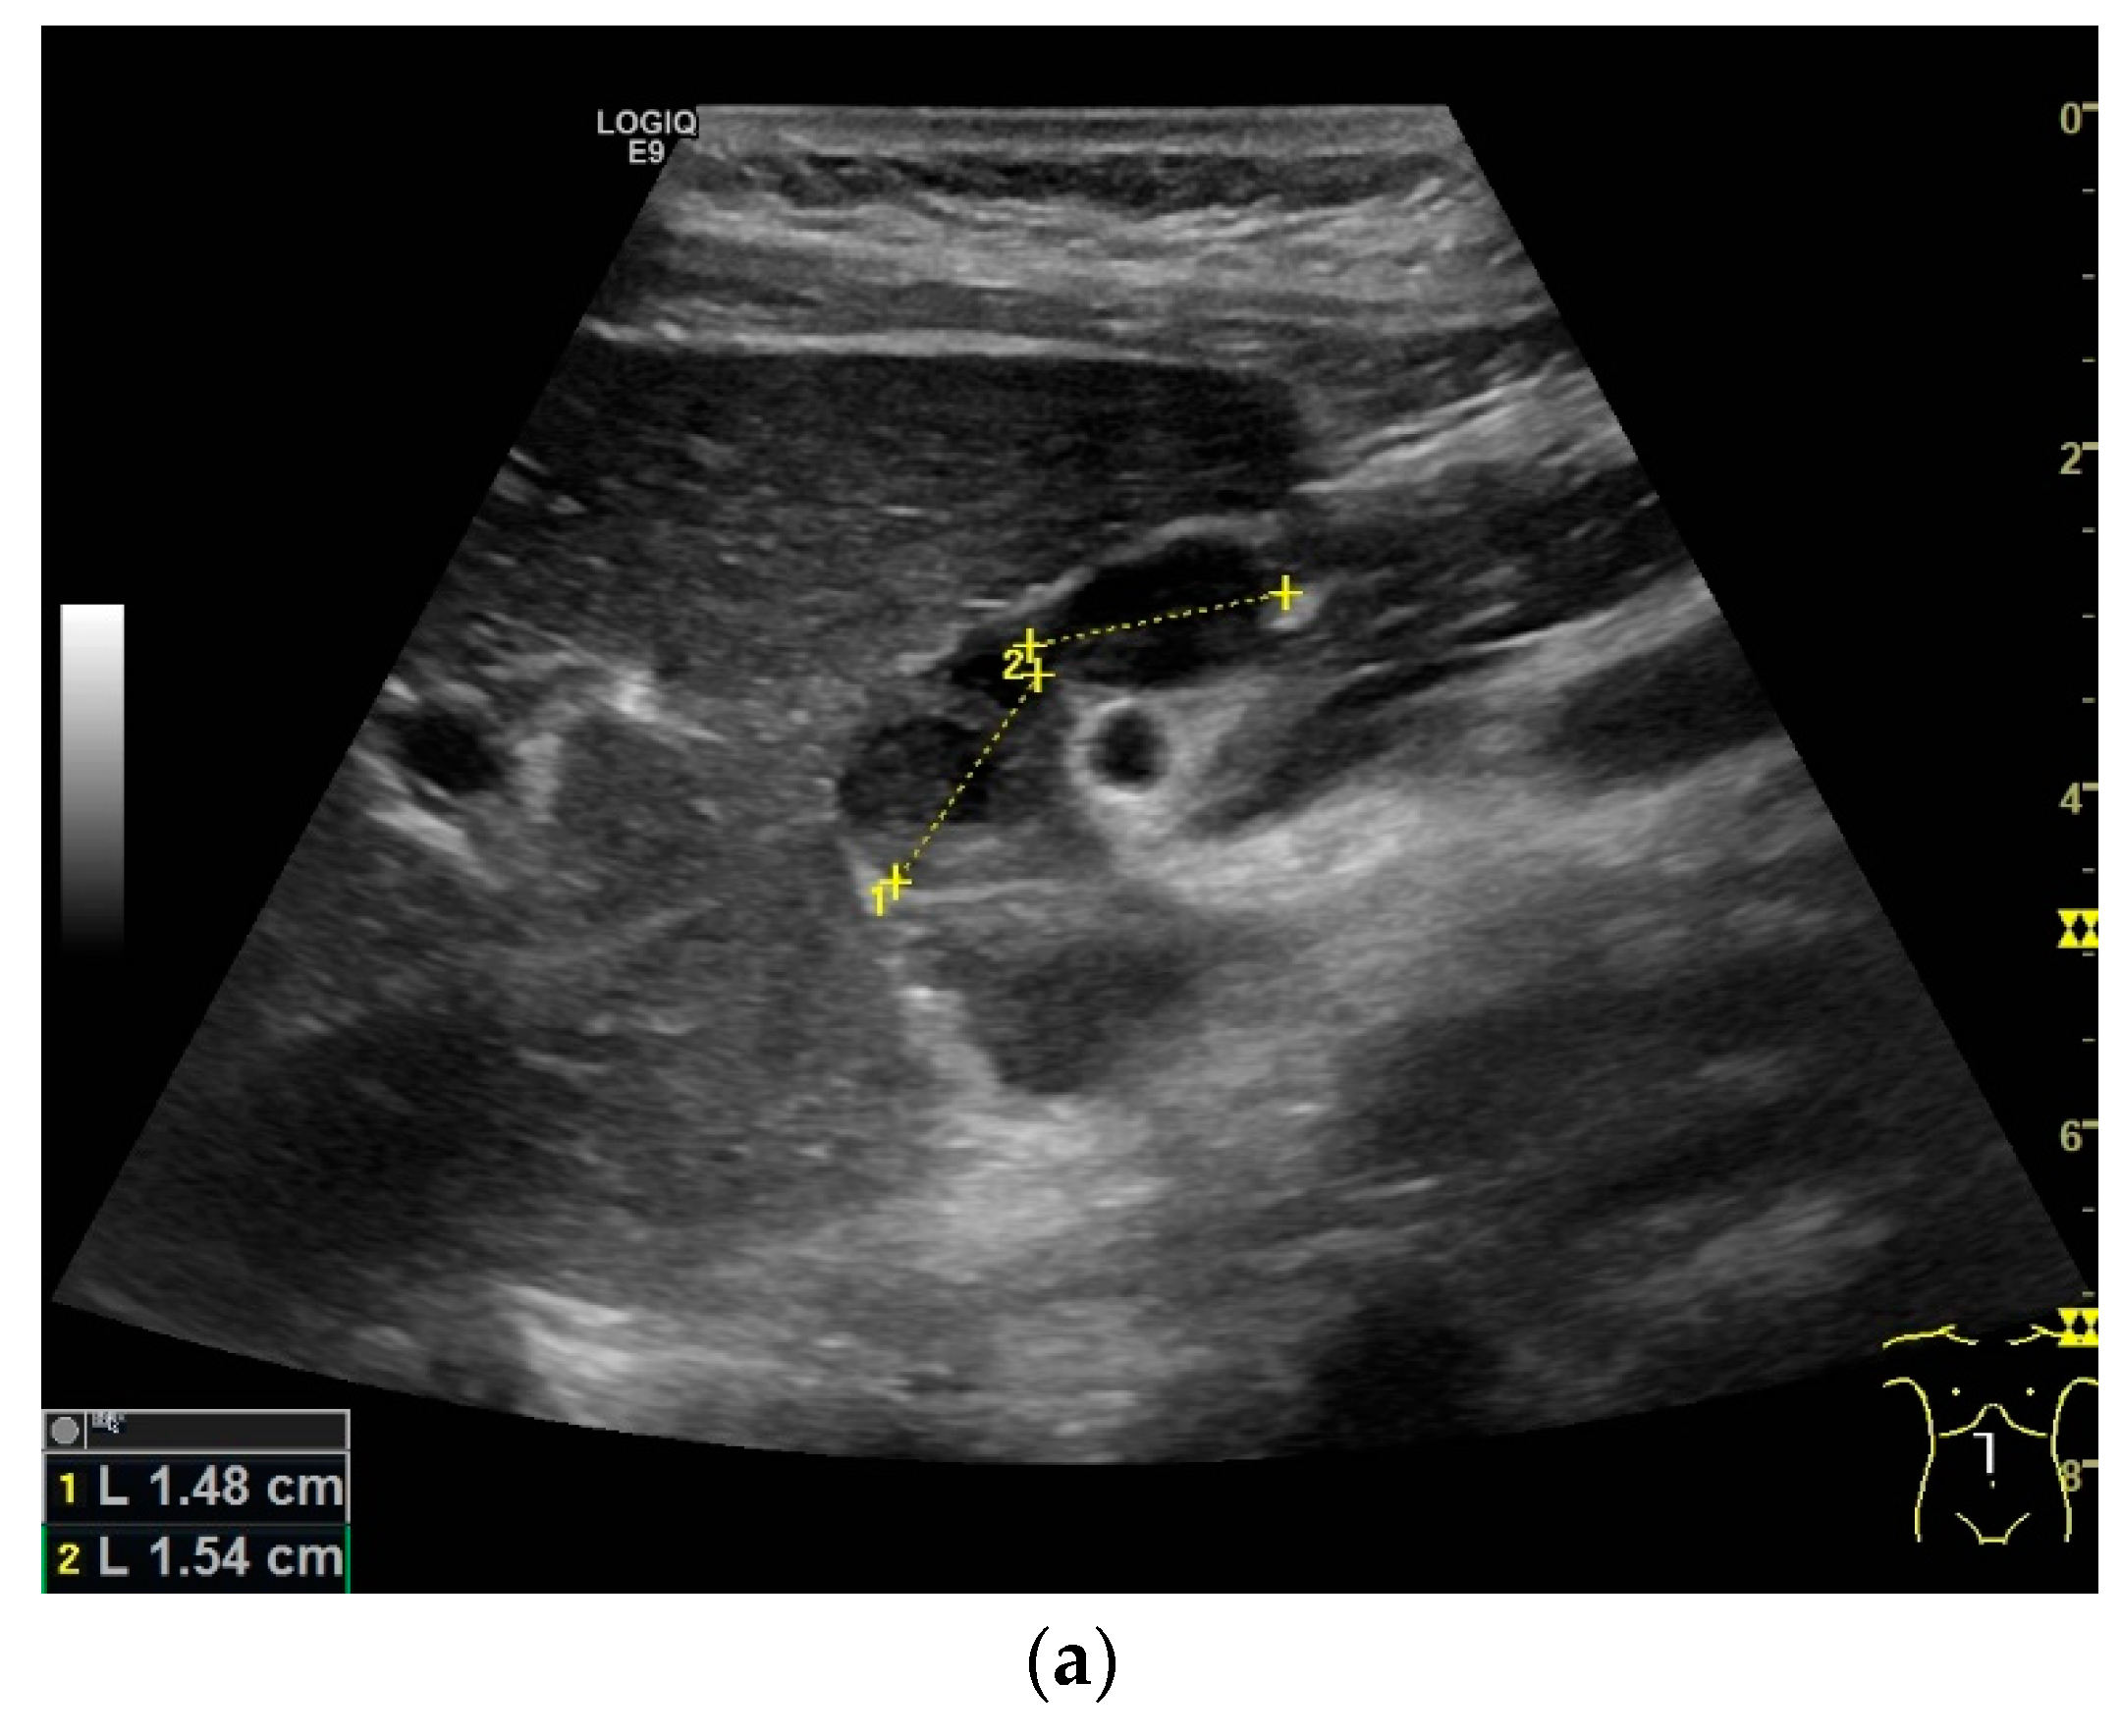

What can be seen sonographically? Ascites can be either diffuse or focal type [Figure 1a,b]. Due to the protein and cell content, these tend to be echogenic, rather than non-echoic. Attention must be paid to enlarged lymph nodes at the same time. Any thickening of the peritoneum and mesentery must be specifically searched for. This also applies to macronodular changes in the peritoneum and mesentery [Figure 1c–h]. The smallest speck-like deposits are usually not visible on ultrasound [36]. With ascites, it may be possible to observe the adhesions [31,37]. Kumar et al. were able to histologically detect granulomatous inflammation in 17/19 (89%) patients using ultrasound-guided needle biopsy of omental thickenings. In a country like India, the authors interpreted this as a manifestation of tuberculosis [32].

Figure 1.

Typical changes in the peritoneum, mesentery, and omentum in patients with tuberculosis. Ascites with pronounced septa (a). Ascites encapsulated between the abdominal wall and colon (b). Omental thickening with non-echoic caseous abscesses and few echogenic contents (c); hypoechoic nodules in hyperechoic thickened peritoneum (d). Significantly thickened hyperechoic peritoneum in B-mode US (right side of image) (marked with arrows). In CEUS, the thickened peritoneum is contrast enhanced in the arterial phase (e). In the parenchymal phase, it shows a decrease in enhancement (f). The thickened hyperechoic peritoneum shows a non-echoic lesion (arrow) (g). In the CEUS, this is not enhanced and instead shows a hyperenhanced rim. This corresponds to caseous necrosis (h).